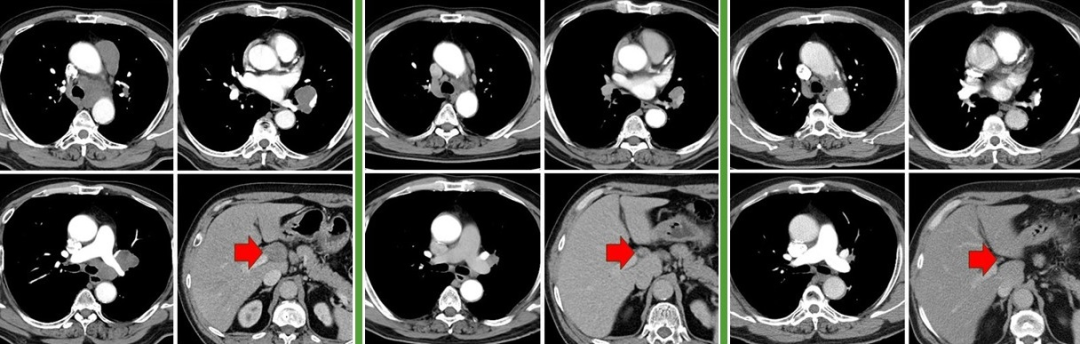

图:左起依次为三线治疗前、三线治疗后、四线治疗前、末次随访